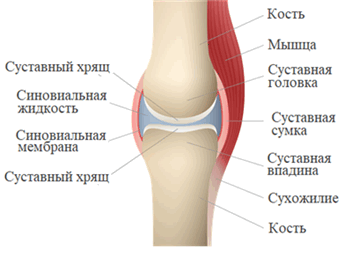

Строение сустава

1.Основные компоненты суставов.

Суставы образуются суставными поверхностями костей, покрытыми гиалиновым хрящом. Концы костей окружены суставной капсулой, которая имеет внутренний синовиальный слой и наружный фиброзный из плотной соединительной ткани. Выстлана суставная сумка мезотелием, он вырабатывает синовиальную жидкость, она заполняет суставную полость. Благодаря жидкости кости близко располагаются друг к другу и происходит скольжение между костями при перемещении в пространстве

- суставные поверхности костей;

- суставную сумку;

- суставную полость;

- суставную (синовиальную) жидкость.

Суставные поверхности соответствуют друг другу по форме и покрыты гиалиновым хрящом. Суставная сумка образует герметичную полость с синовиальной жидкостью. Это способствует скольжению и защищает кость от стирания.

Сустав (синовиальное соединение - греч. sýn - вместе + лат. ovum - яйцо) - подвижное соединение костей скелета. Наука о суставах - артрология (греч. arthron - сустав + logos - учение). Связки - плотные образования из соединительной ткани - укрепляют сустав изнутри и снаружи (связки бывают внутрисуставными и внесуставными).

Поверхности костей в суставе (называемые - суставные поверхности) покрыты гиалиновым хрящом, который снижает трение между костями, выполняет амортизирующую функцию - равномерно распределяет давление.

Суставная сумка (капсула) крепится к суставным поверхностям или в их близи, окружает суставную полость (щелевидное пространство). Суставная сумка изнутри покрыта синовиальной оболочкой, которая секретирует синовиальную жидкость. Синовиальная жидкость заполняет полость сустава, питает сустав, увлажняет его, устраняет трение суставных поверхностей.